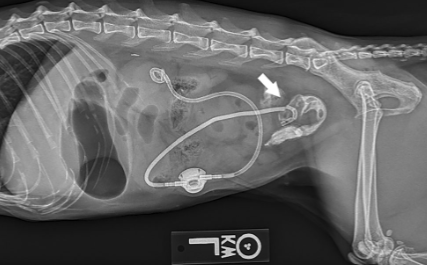

이번에 논문으로 나오는 부작용은 SUB를 장착한 고양이에서 이 SUB 튜브가 유주하여 장분절로 꼽혀버린 상태에 대한 논문이다.

말로 설명하면 무슨 말도 안되는 소린가 싶기에 논문에 나오는 예시 사진을 보면 아래와 같다.

flushing bell을 통해 조영제를 주입하면 이렇게 migration된 끝단이 확인될 수 있으니 이 방법으로 체크해 보는게 추천된다.